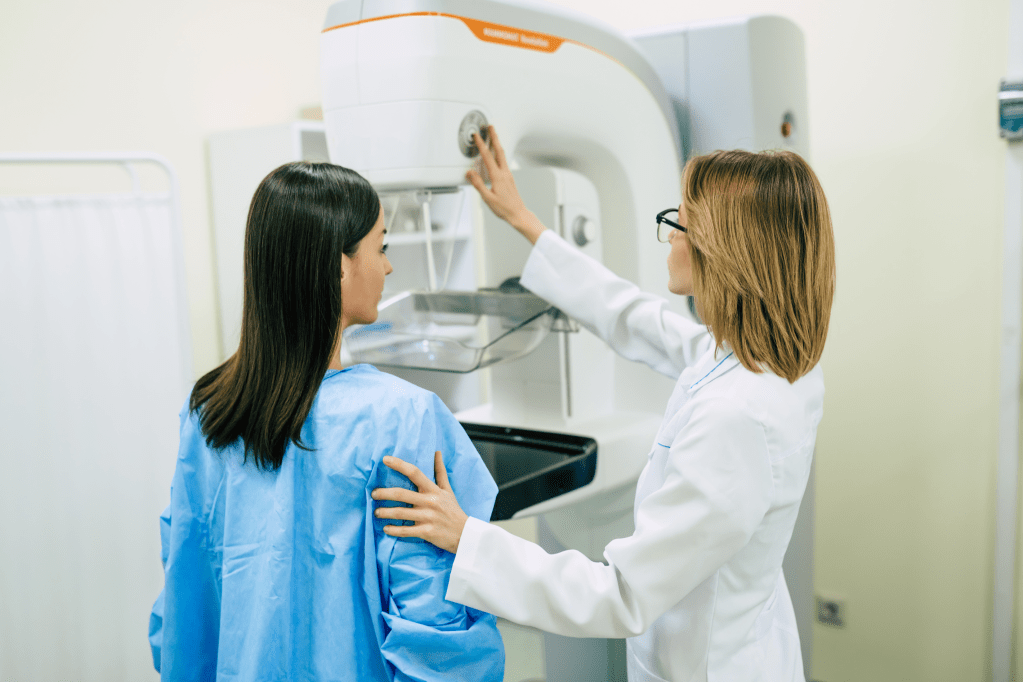

Tomosintesi Mammaria 3D

Il Selenia Dimensions è un mammografo versatile progettato per offrire una tecnica di Tomosintesi rivoluzionaria.

Si è osservato che la Tomosintesi Hologic, in combinazione con la mammografia 2D, riduce considerevolmente il numero dei falsi positivi.

Sono rimasta estremamente soddisfatta della mia esperienza presso il Centro IRI Radiologia per la tomosintesi mammaria 3D. Il personale è stato gentile e premuroso, e mi ha fatto sentire a mio agio durante l’intero processo. I risultati sono stati accurati e mi hanno fornito una grande tranquillità. Consiglio caldamente questo centro a tutte le donne che necessitano di screening mammografico avanzato.

Antonella

Tomosintesi Mammaria 3D